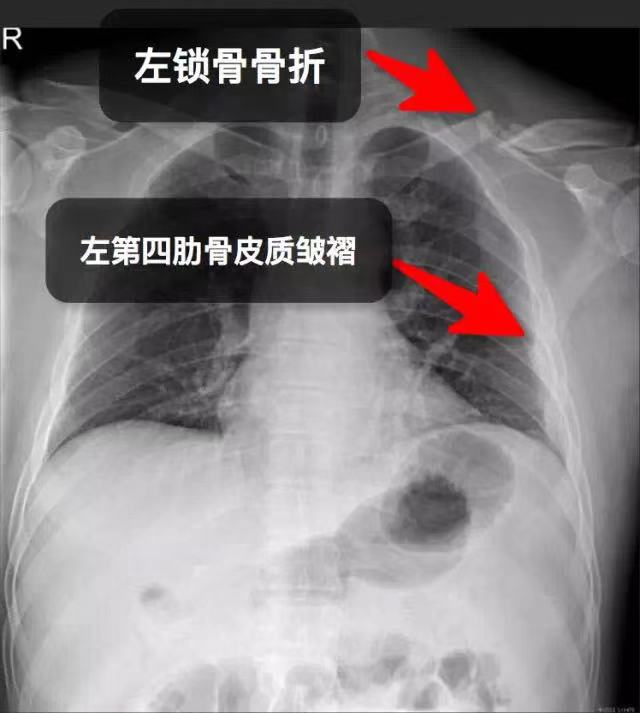

(1)锁骨骨折

肋骨骨折:伤后胸部疼痛,咳嗽及深呼吸时疼痛加重;挤压胸廓时,骨折部分疼痛加剧;有时可合并气、血胸;X线片示肋骨骨折。